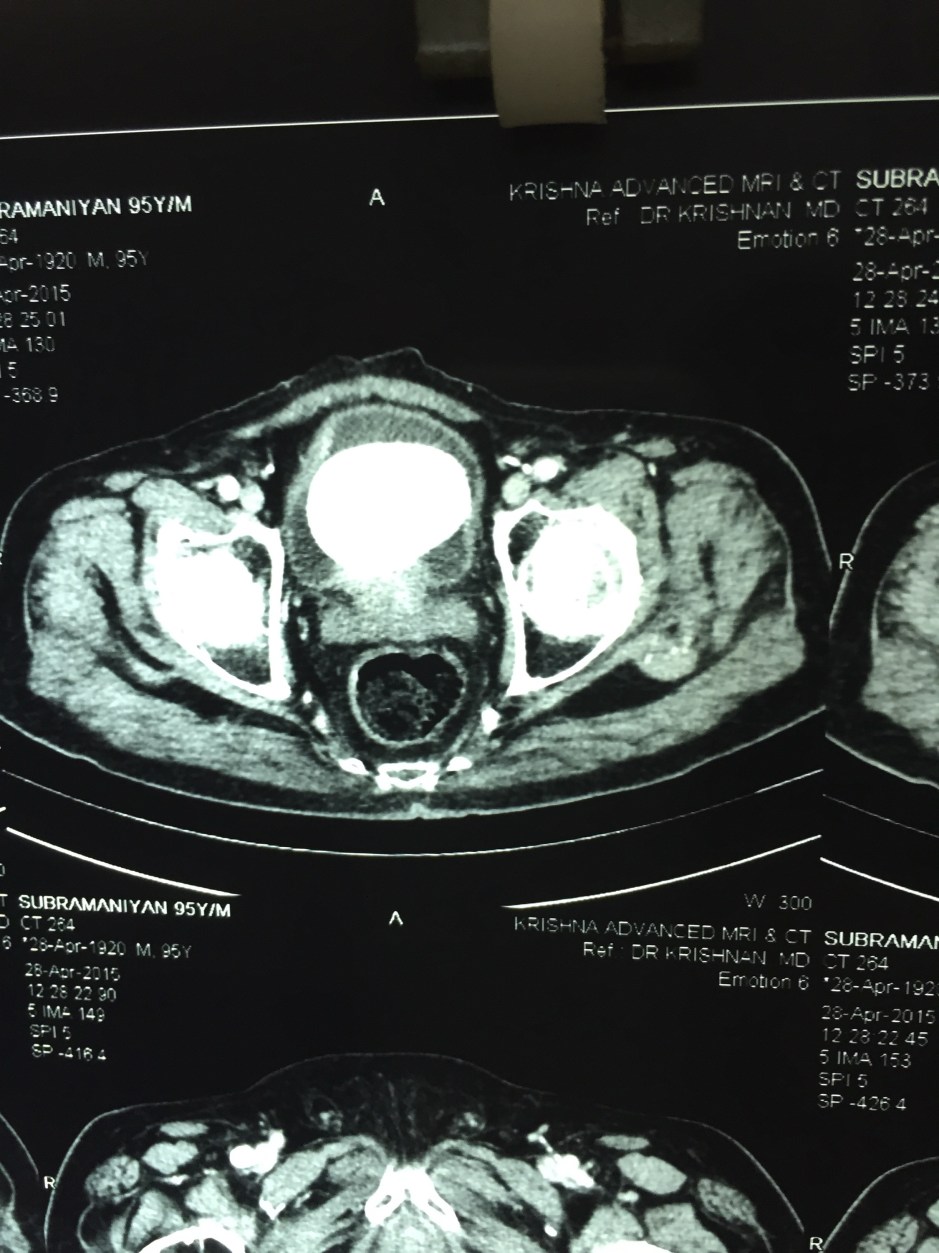

CT scan confirmed the ultrasound findings :

LARGE CALCULUS IN THE URINARY BLADDER WITH MULTIPLE DIVERTICULAE IN THE BLADDER “

The X-ray and the CT scan pictures are given below.